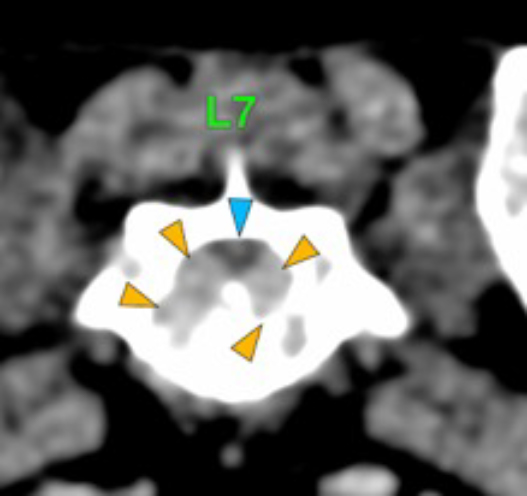

The osteolytic lesions have soft tissue attenuation that shows moderate and slightly heterogeneous post-contrast enhancement. In some of the vertebrae, the lesions cause lysis of the cortex and extend into the vertebral canal (orange arrows) causing variable degree of compression of the spinal cord and cauda equina (blue arrows). At the level of the vertebral bodies of T7, T8, T9 and T12 the lesions extend into the ventral and central aspect of the vertebral canal causing a mild compression of the spinal cord. At the level of T13, L1, L4 and L5 the lesions extend into the ventral and central aspect of the vertebral canal, causing moderate compression of the spinal cord. At the vertebral body of L6 the lesion extends into the ventral and central aspect of the vertebral canal, at the mid-aspect of L6, occupying approx. 90% of the diameter of the vertebral canal causing a severe compression of the cauda equina. At the level of L7, the lesion extends into the ventral and both lateral aspects of the vertebral canal, causing severe compression of the cauda equina.